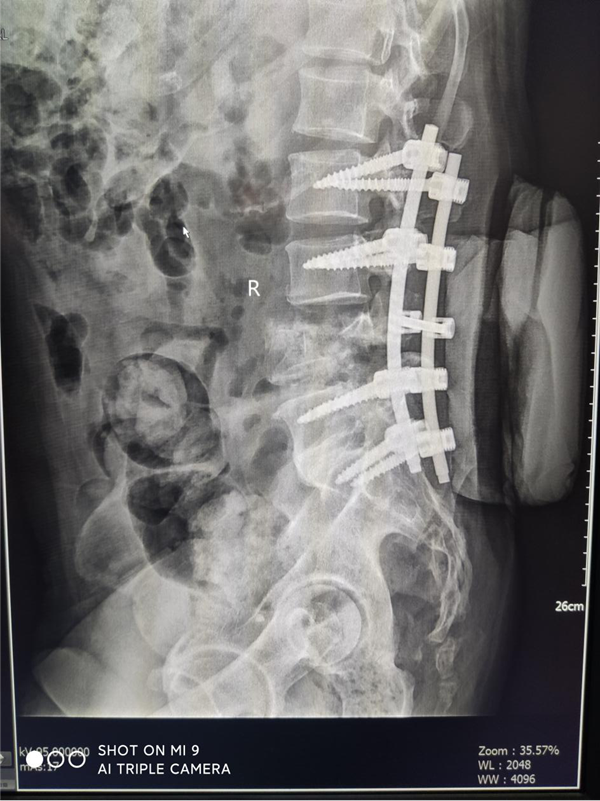

患者刘某,男,55岁,高处坠落致腰部疼痛伴双下肢麻木16小时主诉入院,由于腰部先着地,当时即觉腰部剧烈疼痛伴双下肢麻木和大小便失禁,伤后无昏迷抽搐,无腹痛腹胀,可回忆受伤时情况,伤后未作特殊处理,遂由家属送至我院急诊,查腰椎MRI:腰4椎体爆裂性骨折并继发椎体滑脱,为进一步治疗,急诊收住骨三科。

刘某家属找到了我院骨三科的张纯教授。张教授经过详细了解患者的病情,并判断这是一例严重复杂的脊髓损伤,需要立马进行手术治疗。于是为刘某联系了病房,结合患者年龄大、手术创伤大、出血风险高等特点,经过多次科室讨论及多科室疑难病例会诊,积极联合危重医学科、麻醉科、输血科等相关科室共同制定了周密的手术方案。根据患者病情制定了详细的手术计划及围手术期治疗方案。经过严密的手术前准备,以张纯主任医师为主刀、王伟卓主治医师和黄思华博士为助手,吴刚副主任医师、罗斌医师为麻醉医师,殷敏、马霞为配合护士,黄亚娟、王芳医师为术中诱发电位监护医师的手术团队努力下,手术顺利完成,切开复位内固定保护了严重受伤的脊髓,并进行了脊柱的重建。

图片2_副本.png